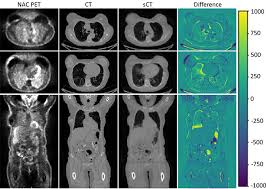

For PET and MRI synthesis, this rivalry ensures that minute aspects such as tissue boundaries, tumour textures, organ contours, and contrast gradients remain faithful to physiological reality. Conditional GANs elevate this process further by linking the output to clinical variables. They allow the generator to craft specific types of abnormalities or normal variations as required for data augmentation. When tuned correctly, GANs honour the underlying physics of the imaging modality so they do not produce biologically incoherent features.

In medical imaging, diffusion models excel when the constraints are strict and realism is non-negotiable. They can rebuild subtle PET intensity distributions or MRI contrasts without falling into the common pitfalls of GANs. Because their creation process unfolds step by step, clinicians and researchers gain more control over what appears in each synthetic scan. When paired with strict domain priors, diffusion models help ensure that synthetic lesions look medically valid and not like random artefacts.